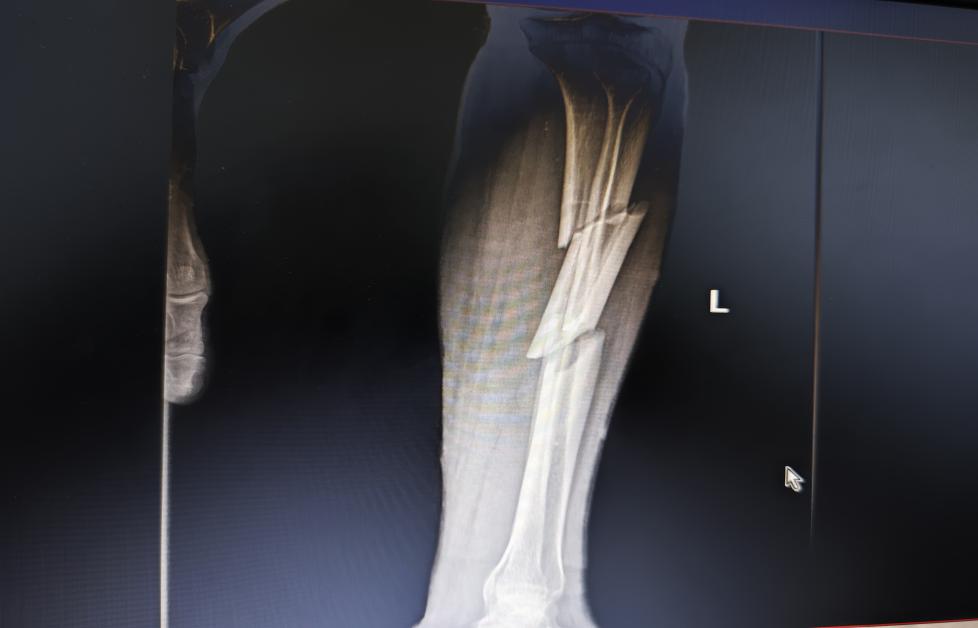

惊险一刻:小腿胫骨竟成“三节棍”

深夜的急诊科,警笛声由远及近。65岁的李叔(化名)因车祸重伤被紧急送至玉林市红十字会医院骨科二区。检查后的结果令人震惊:他的左下肢严重受伤,左侧胫骨和腓骨双双骨折,更为棘手的是,胫骨主干部位出现了两处完全性骨折,断裂的骨骼错位明显,在影像学上呈现出类似“三节棍”的惊心形态,同时伴有多处皮肤软组织挫伤。面对如此复杂的骨与软组织创伤,一场“保膝之战”悄然打响。

术前影像: